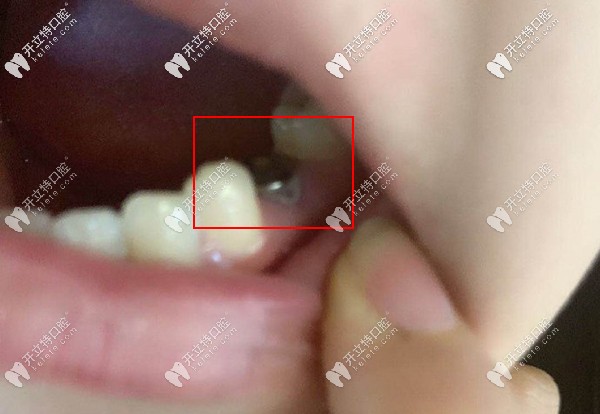

下前磨牙齲壞

這是她給拍的缺牙處種上了種植體

缺牙處種上了種植體